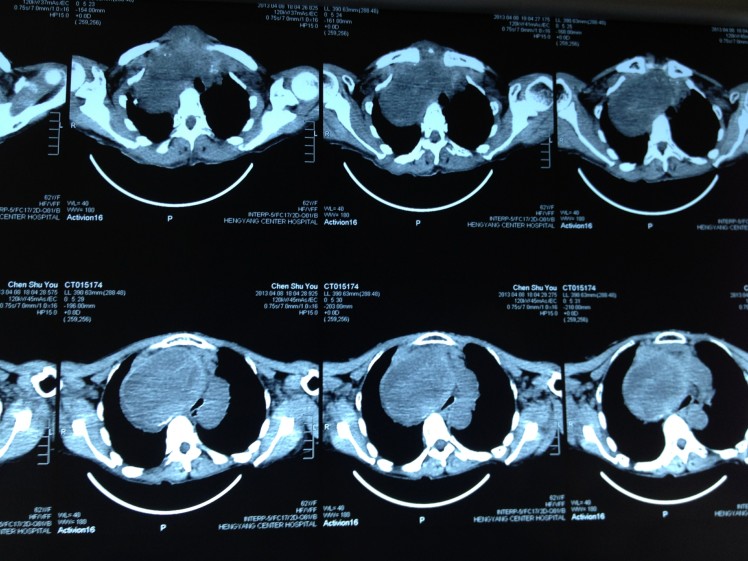

4月8日,62歲的陳阿婆因呼吸困難在家中險些窒息而被家人背送我院乳甲外科就診。陳阿婆發(fā)現(xiàn)頸部雙側腫塊已有30余年,曾就診于省內多家大型醫(yī)院,大多專家建議開胸手術,手術費高達10余萬元,有些醫(yī)院甚至考慮手術難度大、風險高就干脆拒收入院。我院乳甲外科尹軍主任將患者收住院后,會同醫(yī)務部組織了麻醉科、放射科、胸外科、呼吸內科、心內科的專家會診,進行術前討論,制定了周密的手術方案。

手術當日,尹軍主任采用沿頸部橫紋作一橫切口,分離左右舌骨下肌瓣,在保留左側甲狀腺上極一塊如蠶豆大小的正常甲狀腺組織后,對其余雙側病變部分采取切除、止血、從胸骨下方慢慢剝離的方式,最終成功將巨大甲狀腺腫瘤切除,并將軟化氣管懸吊。整個手術過程耗時三小時,術中未輸血,整個甲狀旁腺、喉返神經保護良好。術后病人恢復好,無相關并發(fā)癥,手術后7日患者康復出院。